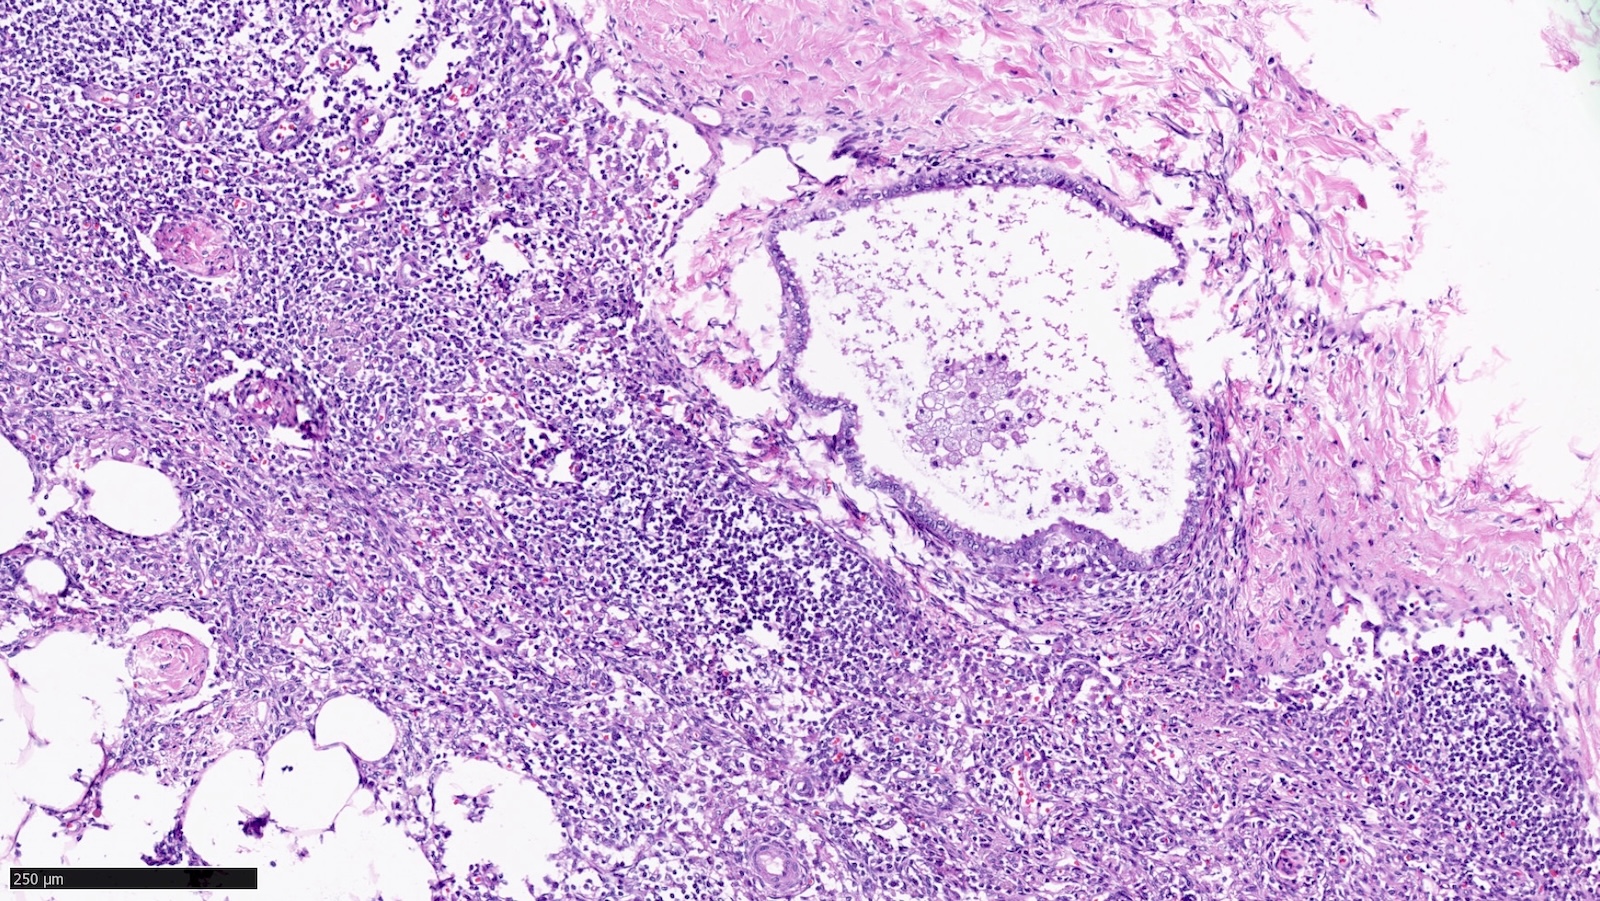

Microscopic (histologic) images

Contributed by Sucheta Srivastava, M.D., Jaya Ruth Asirvatham, M.B.B.S., Rahul Koshy, D.O. and Julie M. Jorns, M.D. (Case #548)

- Benign epithelial inclusions in axillary lymph node (Int J Surg Pathol 2018;26:564, Breast J 2020;26:274):

- These inclusions can be glandular (most common) or squamous epithelium lining cystic lumina

- Glandular inclusions often have a luminal and myoepithelial cell layer

- In some cases, the glandular epithelium shows proliferative changes like usual ductal hyperplasia in the breast

- Endosalpingiosis of axillary lymph nodes (Case Rep Pathol 2016;2016:2856358, Am J Surg Pathol 2010;34:1211, Breast J 2020;26:274):

- Müllerian type glandular inclusions lined by cytologically bland cuboid to columnar epithelial cells that are reminiscent of fallopian tube type lining or coelomic type lining

- Cilia, when present, is a reassuring feature to confirm a benign diagnosis

- Positive for PAX8 and WT1 (good markers of Müllerian origin) and negative for GATA3